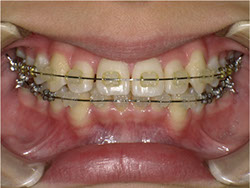

1期治療でスケルトンタイプの拡大装置で歯列拡大後、上下第一小臼歯を抜歯して口元もキレイになりました。

矯正前

矯正中

矯正終了後